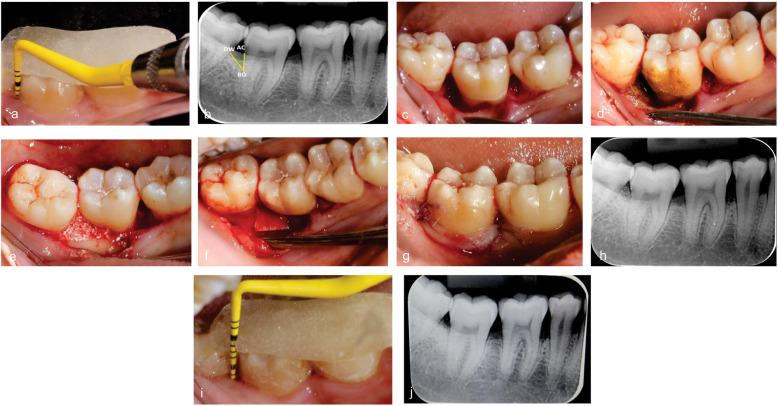

The concept of periodontal regeneration has been revolutionised since the introduction of growth factors and bioactive bone substitutes which ensures optimal regeneration of the diseased periodontium. The aim of the present study was to evaluate the efficacy of Amniotic membrane + Biphasic Calcium phosphate as compared to Collagen membrane + Biphasic Calcium phosphate for the management of periodontal intrabony defects.

METHODS

The results of the present study showed a mean reduction in the PPD of 2.89 ± 0.69 mm in the Collagen membrane + Biphasic Calcium phosphate group and 2.95 ± 0.57 mm in the Amniotic membrane + Biphasic Calcium phosphate group and CAL gain of 2.60 ± 1.43 mm in Collagen membrane + Biphasic Calcium phosphate group 3.18 ± 1.13 mm in the Amniotic membrane + Biphasic Calcium phosphate group at 6 months follow-up with no statistical significance between the groups. In terms of Defect resolution, 98.62 ± 6.51 % was achieved in Collagen membrane + Biphasic Calcium phosphate group and 98.25 ± 7.21 % in Amniotic membrane + Biphasic Calcium phosphate group.

自生长因子和生物活性骨替代物引入以来,牙周再生的概念发生了革命性变化,这确保了患病牙周组织的最佳再生。本研究的目的是评估羊膜+双相磷酸钙与胶原膜+双相磷酸钙治疗牙周骨内缺损的疗效。

根据特定的纳入和排除标准,招募50例全身健康的局限性中度至重度牙周炎患者,这些部位在口腔根尖片(IOPAR)和骨探测中检测到探诊袋深度(PPD)≥6mm且骨内成分≥3mm。通过计算机生成的表格将他们随机分配到胶原膜+双相磷酸钙组和羊膜+双相磷酸钙组。在基线和6个月时测量骨填充量、探诊袋深度变化、临床附着水平。

本研究结果显示,胶原膜+双相磷酸钙组PPD平均降低2.89±0.69mm,羊膜+双相磷酸钙组PPD平均降低2.95±0.57mm;胶原膜+双相磷酸钙组6个月随访时临床附着水平增加2.60±1.43mm,羊膜+双相磷酸钙组增加3.18±1.13mm,两组间无统计学意义。在缺损修复方面,胶原膜+双相磷酸钙组达到98.62±6.51%,羊膜+双相磷酸钙组达到98.25±7.21%。